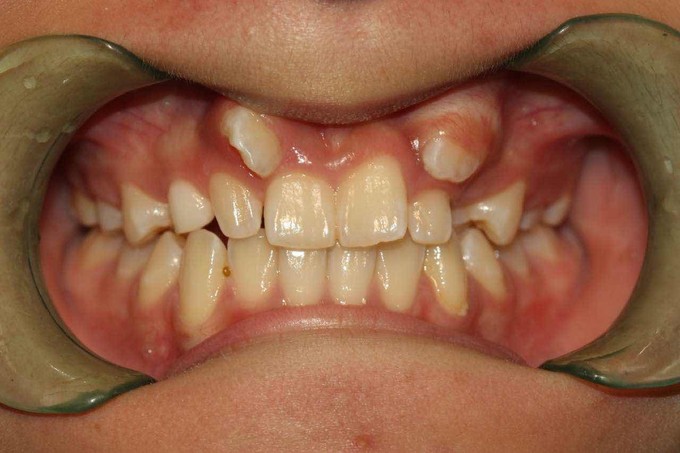

尖牙错位,2过小牙

患者:女,19岁,主诉牙齿不齐,希望矫治。 检查:13根在11和12之间,23根在22唇侧,12和22为过小牙